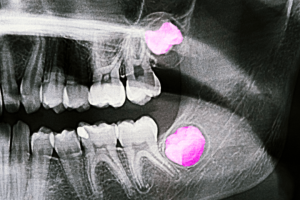

Las muelas del juicio han sido durante años una de las consultas más habituales en clínica dental. Dolor, inflamación, falta de espacio o extracciones preventivas